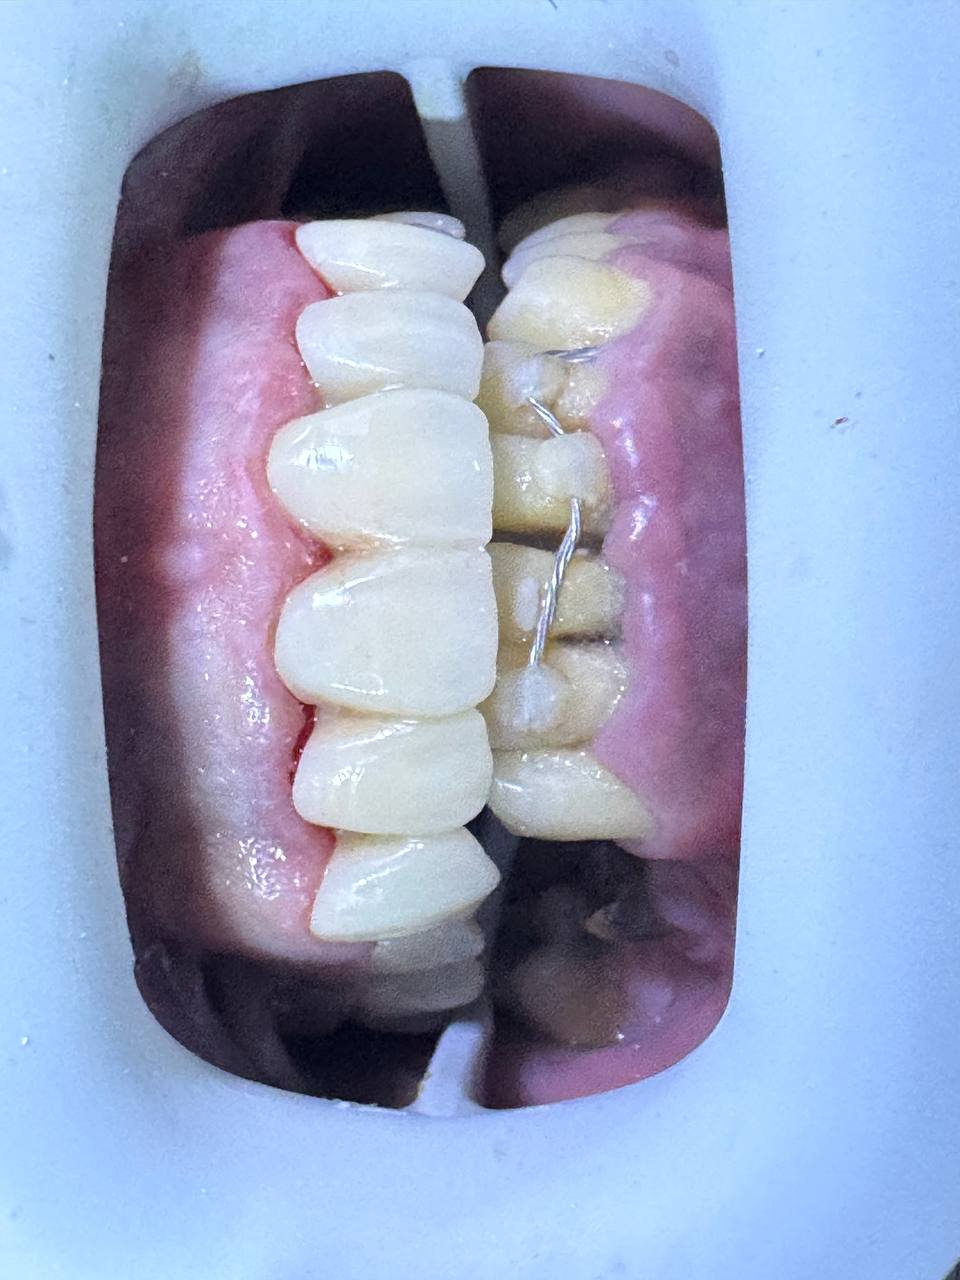

بعد العلاج — ابتسامة مثالية بعد

هكذا كانت النتيجة النهائية

بعد إتمام جميع مراحل العلاج — ابتسامة لم يتوقعها المريض ولا عائلته. من أسنان «ما فيهاش أمل» إلى ابتسامة Zircone متناسقة 100%.

بعد العلاج

«وهكذا كانت النتيجة لي عجبت مراجعنا

والعائلة تاعه»

— Dr. Zaiar Mabrouk | Arzee Dental